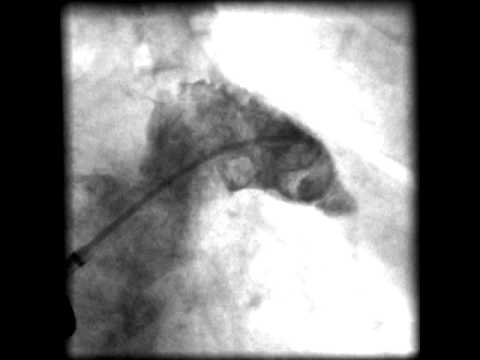

Video 16.17

Video 16.17 Angiographic control.